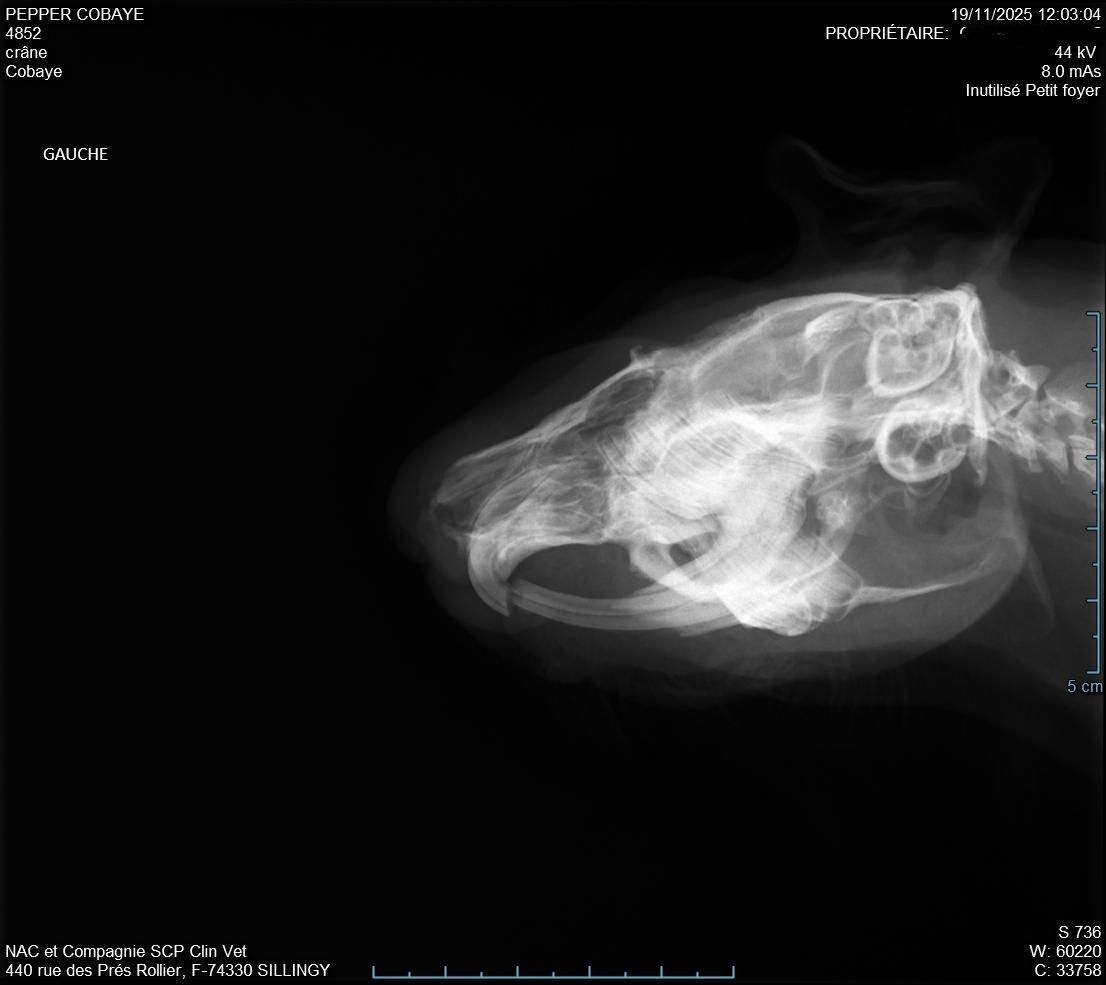

Descendu à 987g donc pas trop bougé depuis la semaine d'avant. La plaie était atone et moins belle que la semaine d'avant (pronostic pas très bon), il a fait des radios pour voir s'il n'y avait pas un problème avec ses dents mais il n'a rien vu, si pas d'amélioration il n'a pas d'autre solution. Nous somme donc repartis pour 10 jours avec un 2eme antibio en continuant le Corylap, Flagyl 125mg/ml 1ml 2x/jour + Contramal 2 à 4 gouttes 2x/jour et toujours Métacam avec le même dosage + Elugel 2x/jour sur la plaie. Changement de gavage pour Critical Care herbivore.

Jour après jour, malgré le gavage son poids n'arrive pas à se stabiliser, il fait grincer ses dents pour ne pas qu'elles poussent de trop et elles sont maintenant en biais alors qu'elles étaient très belles avant.